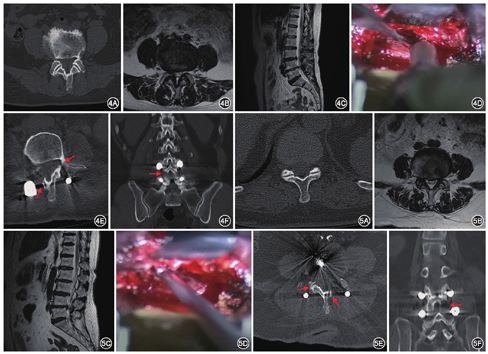

典型病例1:患者男,58岁,腰痛VAS 6分,伴双下肢放射痛,右侧为重(右侧7分,左侧5分),间歇性跛行100 m,ODI 73分。病程5年,进行性加重6个月。手术时间105 min,出血75 ml。术后24个月末次随访时腰部、右下肢、左下肢VAS分别为2、0和1分,ODI 12分(图4)。典型病例2:患者女,62岁,腰痛VAS 5分,伴左下肢麻木无力放射痛(右下肢3分、左下肢8分),ODI 68分。病程3年,手术时间120 min,出血65 ml。术后40个月末次随访时腰部、右下肢、左下肢VAS分别为1、0和2分,ODI 10分(图5)。

各组手术均由同一团队完成。患者全身麻醉俯卧位,腹部悬空,C型臂定位手术节段。后正中切口,脂肪层下于症状侧旁中央纵行切开腰骶筋膜,A组钝性分离最长肌、腰髂肋肌肌间隙,手指触及横突及关节突,置入套筒。B组钝性分离最长肌与多裂肌肌间隙,置入套筒。两组均在显微镜辅助下暴露上下关节突及部分椎板,骨刀截除部分下关节突,Kerrison咬骨钳咬除部分椎板及黄韧带,暴露同侧神经根及部分硬膜囊,行神经根松解及根管减压,切除椎间盘处理终板行椎间融合。倾斜套筒,调整显微镜角度,使用Kerrison咬骨钳潜行咬除椎板下黄韧带,使用神经剥离子保护硬膜囊,直视下使用高速磨钻减压中央管及对侧神经根管(图3)。常规椎弓根钉固定,留置引流管后拔出套筒,逐层关闭切口。术后24~48 h内根据引流量拔除引流,术后第2天佩戴腰部支具下床活动并进行功能锻炼。

最长肌与腰髂肋肌肌间隙较Wiltse肌间隙旁开约1.2 cm,肌间隙内无重要神经血管走行。此间隙深面可见多裂肌,沿多裂肌表面可触及横突及关节突,经此间隙可到达L2/3至L5/S1各节段椎间孔区。L5/S1节段因髂嵴阻挡,须将套筒向尾倾20°~25°到达椎间孔区。模拟手术套筒放置,Wiltse肌间隙入路套筒最大倾斜角度为40°,LPA入路套筒最大倾斜角度为65°(图2)。